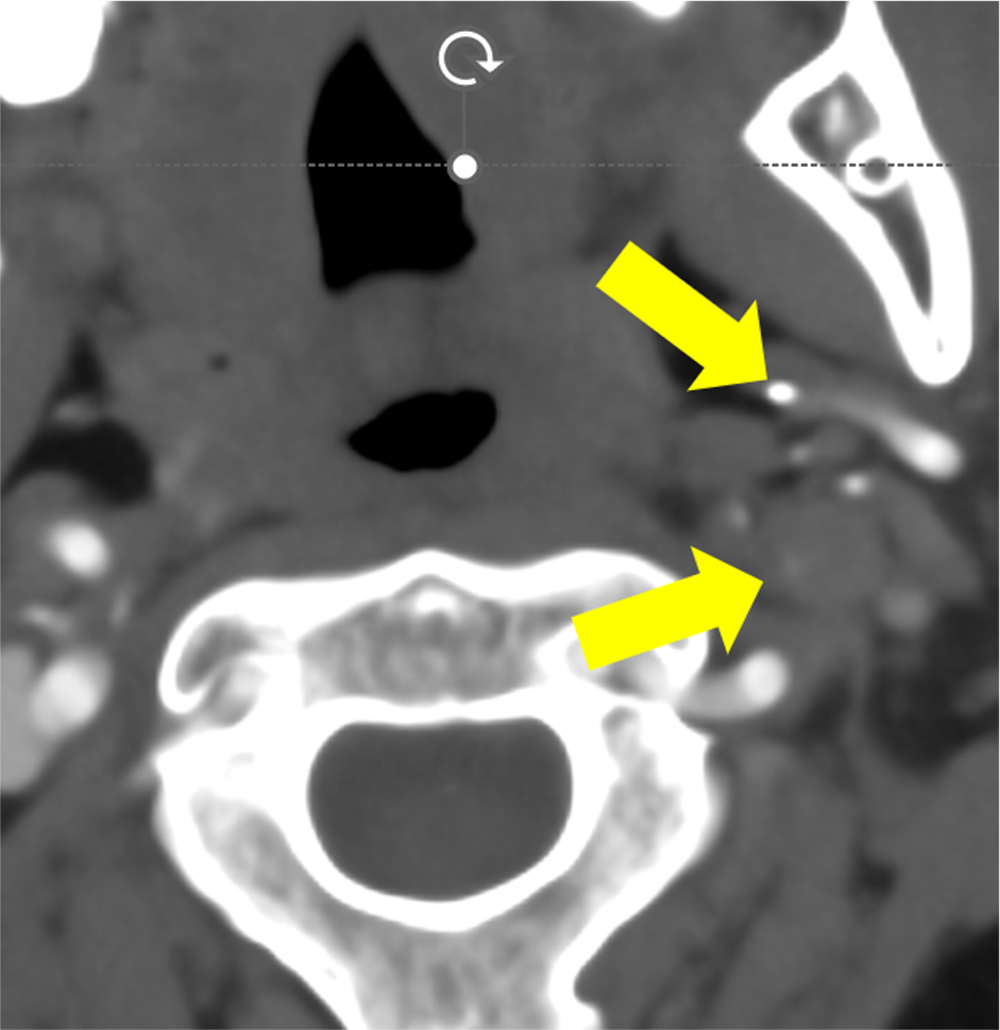

交通外傷後に構音障害が持続し、脳梗塞と診断された患者。内頸動脈解離による閉塞が疑われ、造影CTが施行された。造影CTで左内頸動脈の閉塞を指摘、原因として解離が疑われた。

また、茎状突起の過長はないが、解離部近傍に茎状突起先端が近接しており、茎状突起による内頸動脈解離が疑われたため、茎状突起切除術後に狭窄部ステント留置となった。

過長茎状突起に関連した内頸動脈解離は稀と言われているが、その報告数は近年増加してきている。本症例でも茎状突起に過長はないものの、内頸動脈に近接していた。

DSAでは周囲骨が subtractionされ、頸部エコーや MRA においては茎状突起が描出されないため、茎状突起の評価が十分に行うことができない。そのため、内頸動脈解離急性期での診断の際に、過長茎状突起の有無の評価や内頸動脈と茎状突起の位置を描出するのにCTA が有効であると考えられる。

茎状突起周囲は下顎骨や乳様突起に囲まれており、3D 画像のみでなくCTAの axial view の元画像などで茎状突起と頸動脈が近接していないか確認するのがよいと考えられる。